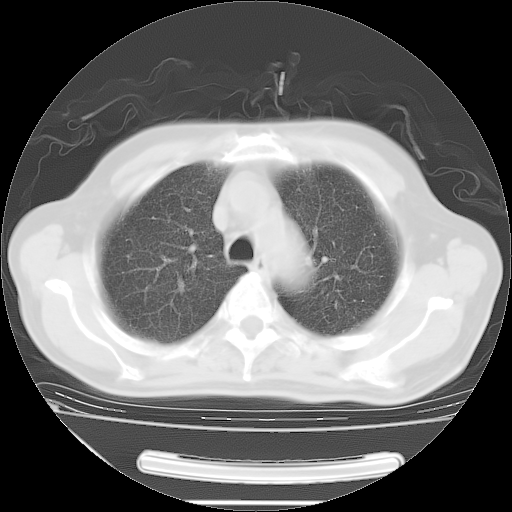

今天复查肺部CT,发现双肺广泛磨玻璃样改变。所以我把3月19日和5月9日相隔50天的肺部CT上传。请大家会诊。

5月9日肺部CT(在4月27日齐鲁医院肺部CT描述部分肺组织磨玻璃样改变,12天后肺组织广泛磨玻璃样改变)

2009年5月9日肺部CT

大致读了系列胸部CT:纵隔窗无明显异常,肺窗:从4、27至今:主要是双肺中下野外带可见毛玻璃样改变,目前处于急性肺泡炎阶段,至于原因考虑1、结替组织或胶原血管性疾病所致?2、恶性疾病如恶组在肺部所致的表现或细支气管肺泡癌?3、药物或其它原因如肺蛋白沉着症所致肺泡炎目前不太可能?总之,明天就去请我院的呼吸科、感染科、血液科和临免专家会诊哈。